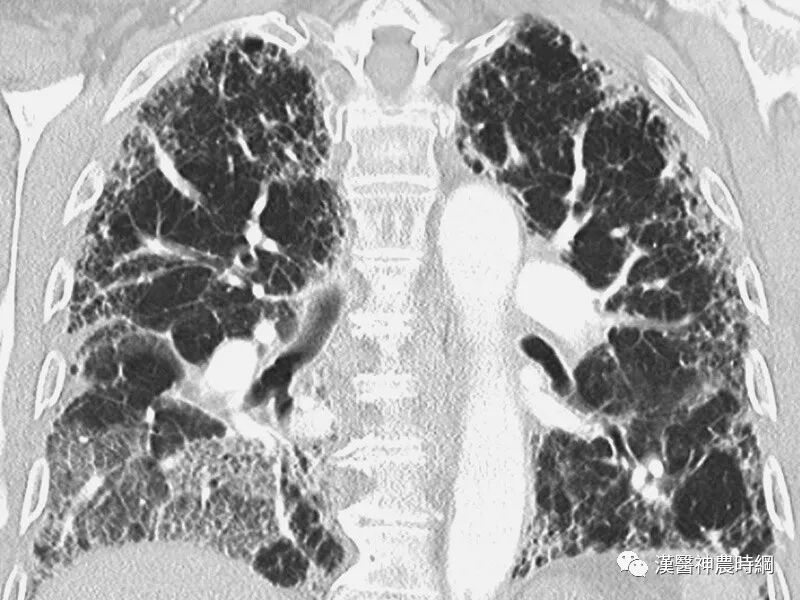

大多数间质性肺疾病都有共同的病理基础过程。初期损伤之后有肺泡炎,随着炎性-免疫反应的进展,肺纤维化泡壁、气道和血管最终都会发生不可逆的肺部瘢痕(纤维化)。炎症和异常修复导致肺间质细胞增殖,产生大量的胶原和细胞外基质。肺组织的正常结构为囊性空腔所替代,这些囊性空腔有增厚的纤维组织所包绕,此为晚期的“蜂窝肺”。肺间质纤维化和“蜂窝肺”的形成,导致肺泡气体-交换单元持久性的丧失。

肺纤维化发展过程中肺泡塌陷是失去上皮细胞的结果。暴露的基底膜可直接接触和形成纤维组织,大量肺泡塌陷即形成密集的瘢痕,形成蜂窝样改变。蜂窝样改变是瘢痕和结构重组的一种表现。肺脏损伤后,修复的结果是纤维化还是恢复正常解剖结构,取决于肺泡内渗出物及碎屑能否有效清除。

一般情况下,肺纤维化早期出现肺泡炎,肺泡内有浆液和细胞成分,肺间质内有大量单核细胞,部分淋巴细胞,浆细胞,肺泡巨噬细胞等炎性细胞浸润,肺泡结构完整。进入晚期,慢性炎症已减轻,肺泡结构为坚实的胶原代替,肺泡壁被破坏,形成扩张的蜂窝肺。胶原、细胞外基质、成纤维细胞分布在间质中,肺泡上皮化生为鳞状上皮。

早期虽有呼吸困难,但X线胸片可能基本正常;中后期出现两肺中下野弥散性网状或结节状阴影,偶见胸膜腔积液,增厚或钙化。肺组织纤维化的严重后果,导致正常肺组织结构改变,功能丧失。就是大量没有气体交换功能的纤维化组织代替肺泡,导致氧不能进入血液。患者呼吸不畅,缺氧、酸中毒、丧失劳动力、靠呼吸机生存,最后衰竭、死亡。